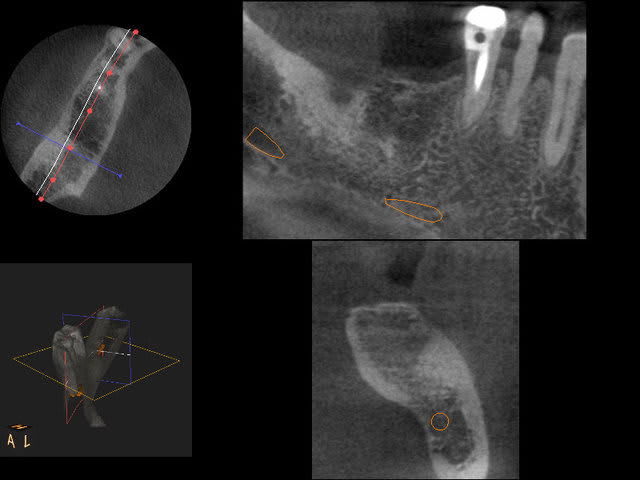

En ce qui concerne la précision, dans ce cas là et pour eviter une augmentation, j ai du placer l implant en mesio palatinal ( voir radio initiale)

En mesurant la hauteur de l os dans le septum ( dans le DVT), celui était seulement de 3 mm. Voilà pourquoi l´implant n est pas dans le septum. L´os a été condensé,la stabilité primaire a donc pu atteindre 50 Ncm.